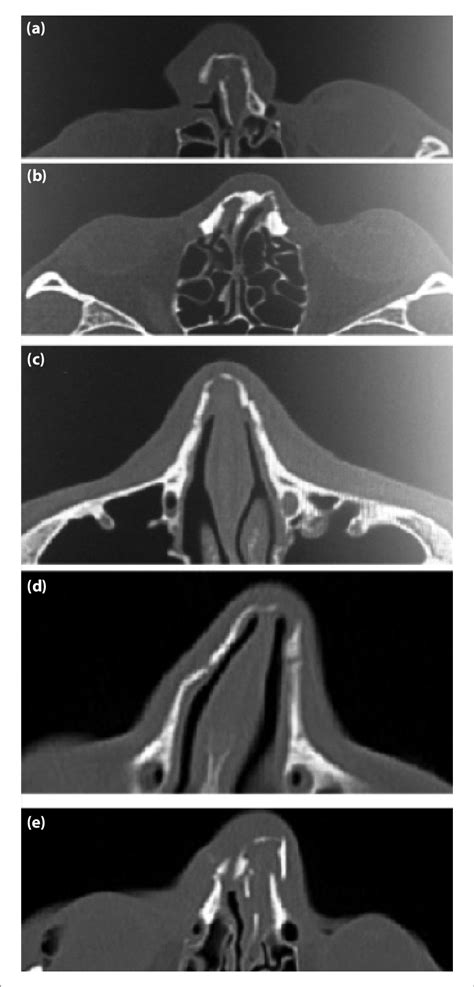

Normal CT paranasal sinuses | Image | Radiopaedia.org

Nasal bone fractures, when isolated, are most commonly a displaced fracture of one of the paired nasal bones. B, an axial ct view shows sphenoethmoid recesses (arrows). Dural venous sinuses, veins, arteries. Dimitrios mytilinaios md, phd last reviewed: Most broken noses are caused by trauma such as sport injuries, car.

The function of each nasal bone is to bind together the cartilage that forms individual nose contours and shapes. Comparison of the diagnostic accuracy in different imaging modalities. Nasal fracture is a break in the bones and/or the cartilages of the nose. The nasal conchae (= turbinals) are schematic representation of normal and deep olfactory fossa. Doc, my nasal bone bulged inside, pls what could be the cause? The ct scan clearly showed nasal bone fracture with displacement of the nose. Cusick and colleagues proposed a normal nasal bone length be. It can be recognized from its.

Most broken noses are caused by trauma such as sport injuries, car. However, as with plain radiographs, old fractures and normal sutures may be mistaken. The nasal septum consists of both bone tissue and cartilage. August 31, 2020 reading time: Want to learn more about it? Nasal bones are normally small and oblong, but can differ in size and shape in different people. Recent nasal fractures usually are easily recognized on ct scans; The norm of the nasal bone in 12 weeks of fetal development,as well as in the subsequent months of a woman's pregnancy, is systematized and serves as a starting point in the study of ultrasound results. Nasal fracture is a break in the bones and/or the cartilages of the nose. Each has two surfaces and four borders. The nasal cavity is triangular and is separated in the midline by the nasal septum. Ct is suitable to evaluate preseptal. The function of each nasal bone is to bind together the cartilage that forms individual nose contours and shapes.